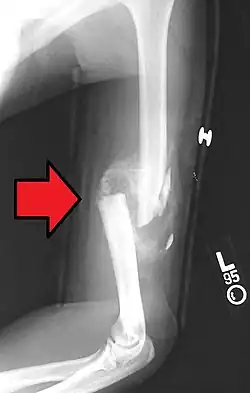

A displaced supracondylar fracture in a child

Distal humerus fractures usually occur as a result of physical trauma to the elbow region. If the elbow is bent during the trauma, then the olecranon is driven upward, producing a T- or Y-shaped fracture or displacing one of the condyles.[7]

Fractures of the humerus are classified based on the location of the fracture and then by the type of fracture. There are three locations that humerus fractures occur: at the proximal location, which is the top of the humerus near the shoulder, in the middle, which is at the shaft of the humerus, and the distal location, which is the bottom of the humerus near the elbow.[9] Proximal fractures are classified into one of four types of fractures based on the displacement of the greater tubercle, the lesser tubercle, the surgical neck, and the anatomical neck, which are the four parts of the proximal humerus, with fracture displacement being defined as at least one centimeter of separation or an angulation greater than 45 degrees. One-part fractures involve no displacement of any parts of the humerus, two-part fractures have one part displaced relative to the other three; three-part fractures have two displaced fragments, and four-part fractures have all fragments displaced from each other.[13][14][3] Fractures of the humerus shaft are subdivided into transverse fractures, spiral fractures, "butterfly" fractures, which are a combination of transverse and spiral fractures, and pathological fractures, which are fractures caused by medical conditions.[12] Distal fractures are split between supracondylar fractures, which are transverse fractures above the two condyles at the bottom of the humerus, and intercondylar fractures, which involve a T- or Y-shaped fracture that splits the condyles.[7]